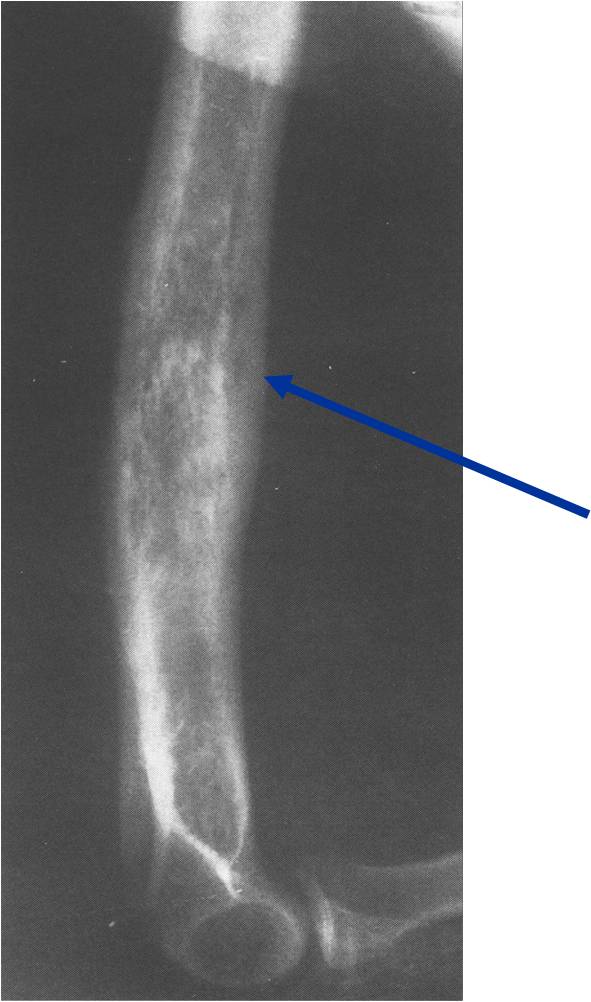

Permeative/Moth eaten lesion Reactive sclerosis (mixed lysis and sclerosis) Slight periosteal reaction

- Permeative or moth eaten bone destruction (55%)

- Geographic (11%); Blow out (1%); Blastic (2%); Normal XR (5%)

- Periosteal reaction—may look benign

- Interrupted or solid single layer (66%)

- Onion Skin 10%